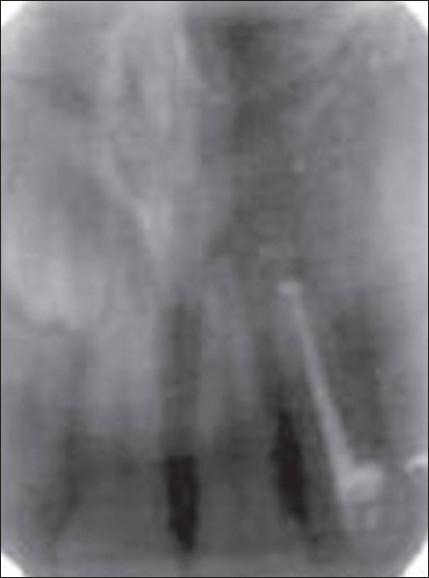

Calcium phosphate ceramics like hydroxyapatite and beta -tricalcium phosphate (beta -TCP) possess mineral composition that closely resembles that of the bone. They can be good bone substitutes due to their excellent biocompatibility. Biphasic calcium phosphate is a bone substitute which is a mixture of hydroxyapatite and beta -tricalcium phosphate in fixed ratios. Studies have demonstrated the osteoconductive potential of this composition. This paper highlights the clinical use of biphasic calcium phosphate as a bone substitute in periapical surgery.

磷酸钙陶瓷,如羟基磷灰石和β-磷酸三钙(β-TCP),具有与骨骼极为相似的矿物质组成。由于其出色的生物相容性,它们可以成为良好的骨替代物。双相磷酸钙是一种骨替代物,它是按固定比例混合的羟基磷灰石和β-磷酸三钙。研究已经证明了这种组合物的骨传导潜力。本文重点介绍了双相磷酸钙作为骨替代物在根尖手术中的临床应用。